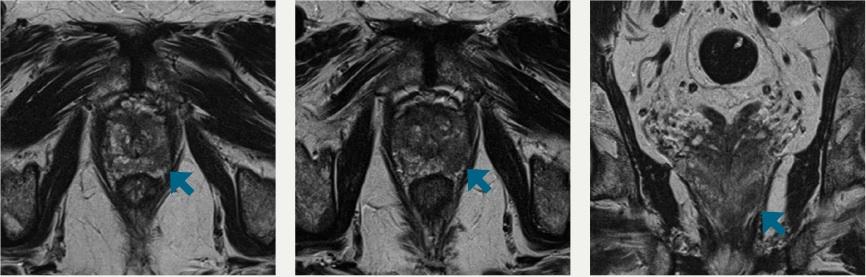

“MRI technology gives us the ability to view detailed cross-sectional images of the prostate and provide a much more accurate view of the type of tumor we’re dealing with.

“In addition, MRI-guided biopsies are a game changer. We now have the ability to pinpoint exactly where the tumor is and biopsy the precise target rather than the traditional ‘shotgun approach’ of ultrasound-guided biopsies,” Winokur said.